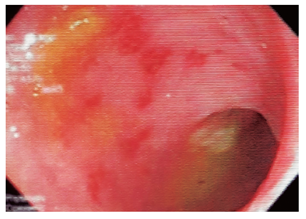

Si en la primera fase no se diagnostica una infección por patógenos y la diarrea persiste y es severa, se deben realizar estudios endoscópicos o radiológicos 34,37. Las guías sobre el estudio endoscópico de la diarrea de la American Society for Gastrointestinal Endoscopy (ASGE) 37 recomiendan realizar inicialmente sigmoidoscopia en pacientes con VIH, pero aclaran que, si la sigmoidoscopia no es positiva y la probabilidad de infección oportunista es alta, se debe realizar colonoscopia con biopsias de íleon y colon, y EGD con biopsias de duodeno (Figura 3 ).

Varios estudios han demostrado la utilidad de los procedimientos endoscópicos en este contexto. Se debe aclarar que no hay un patrón endoscópico típico de infección por oportunistas, por tanto, siempre se deben tomar biopsias. Se sugiere que la infección por Salmonella predomina en el colon derecho y va desde un eritema hasta ulceraciones. La infección por amebas suele afectar el ciego y rectosigmoide, con ulceraciones y zonas de necrosis (Figura 4 ). El CMV puede generar ulceraciones que predominan en el colon izquierdo (Figura 5 ). El rendimiento de la colonoscopia va desde el 27% al 39%, y el CMV es el germen más común 38.

Un estudio comparó los exámenes microbiológicos en la materia fecal con las biopsias por endoscopia y se encontró que estos últimos tienen mayor rendimiento en pacientes con CD4 <200 células/mm339. Otro estudio diagnosticó una infección oportunista por métodos endoscópicos en 21/48 pacientes (44%; intervalo de confianza [IC] 95%: 30%-58%). La colonoscopia encontró el diagnóstico en 13 pacientes, incluido el CMV en 9 de ellos. En la mayoría de pacientes se realizó el diagnóstico por biopsias del rectosigmoide. La EGD diagnosticó una infección por Microsporidium en 7 pacientes y Criptosporidium en 2 pacientes 40.